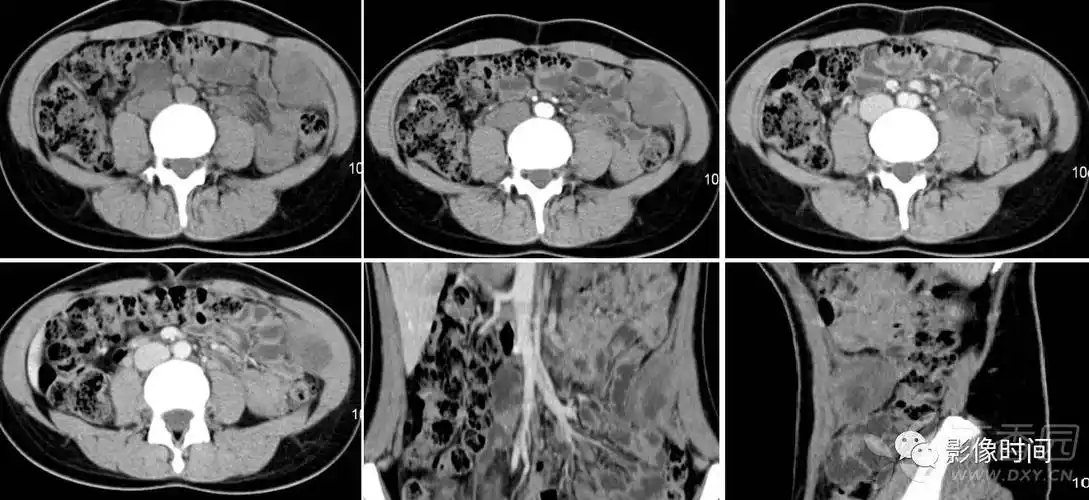

优质一例韧带样纤维瘤,您有见过么?